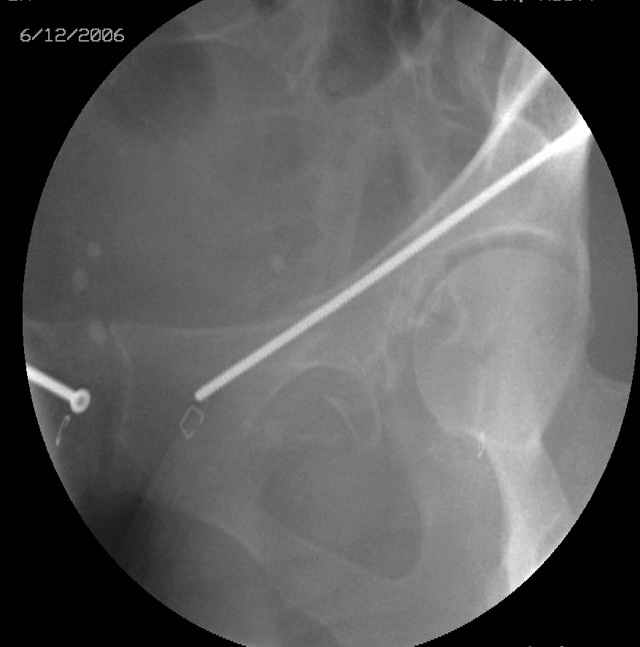

OK, now we're inserting the drill percutaneosuy using a sleeve. This fluoro shot is not for this patient (notice no clamp) but I was too lazy to go searching the PACS for one with the clamp on, so pretend...I'll save the next ones and send along...the imaging is the same and the clamp doesn't obstruct imaging other than very rarely...you can always tilt the C-arm a bit to clear it if the clamp obstructs the exact spot that you'd like to see. We'll assume that everyone knows the safe zone for a medullary ramus screw. Use a calibrated drill and sleeve of known length to simplify your life...or use Alex's fancy cannulated screws...I like 3.5mm screws because the oscillating 2.5mm drill bounces and remains intraosseus when it oscillates and contacts endosteal cortical ramus... so will the screw, and like a long bent screw IF the fracture is clamped... if unclamped, when the screw contacts the endosteum, it pushes the reduction apart instead of bouncing. The big 7mm cannulated screws fit few patients and extrude...we very rarely use them any more...you'll see an old one later.

Prone Obturator-Outlet

Screw insertion using the obturator-outlet combination image.

12.Prone Obturator-Outlet

Same with a contoured pelvic reconstruction plate applied and tensioned.

Prone Iliac Oblique

The other oblique reveals the extra-articular implants.... you know the AC screw is extra-articular from the other views.